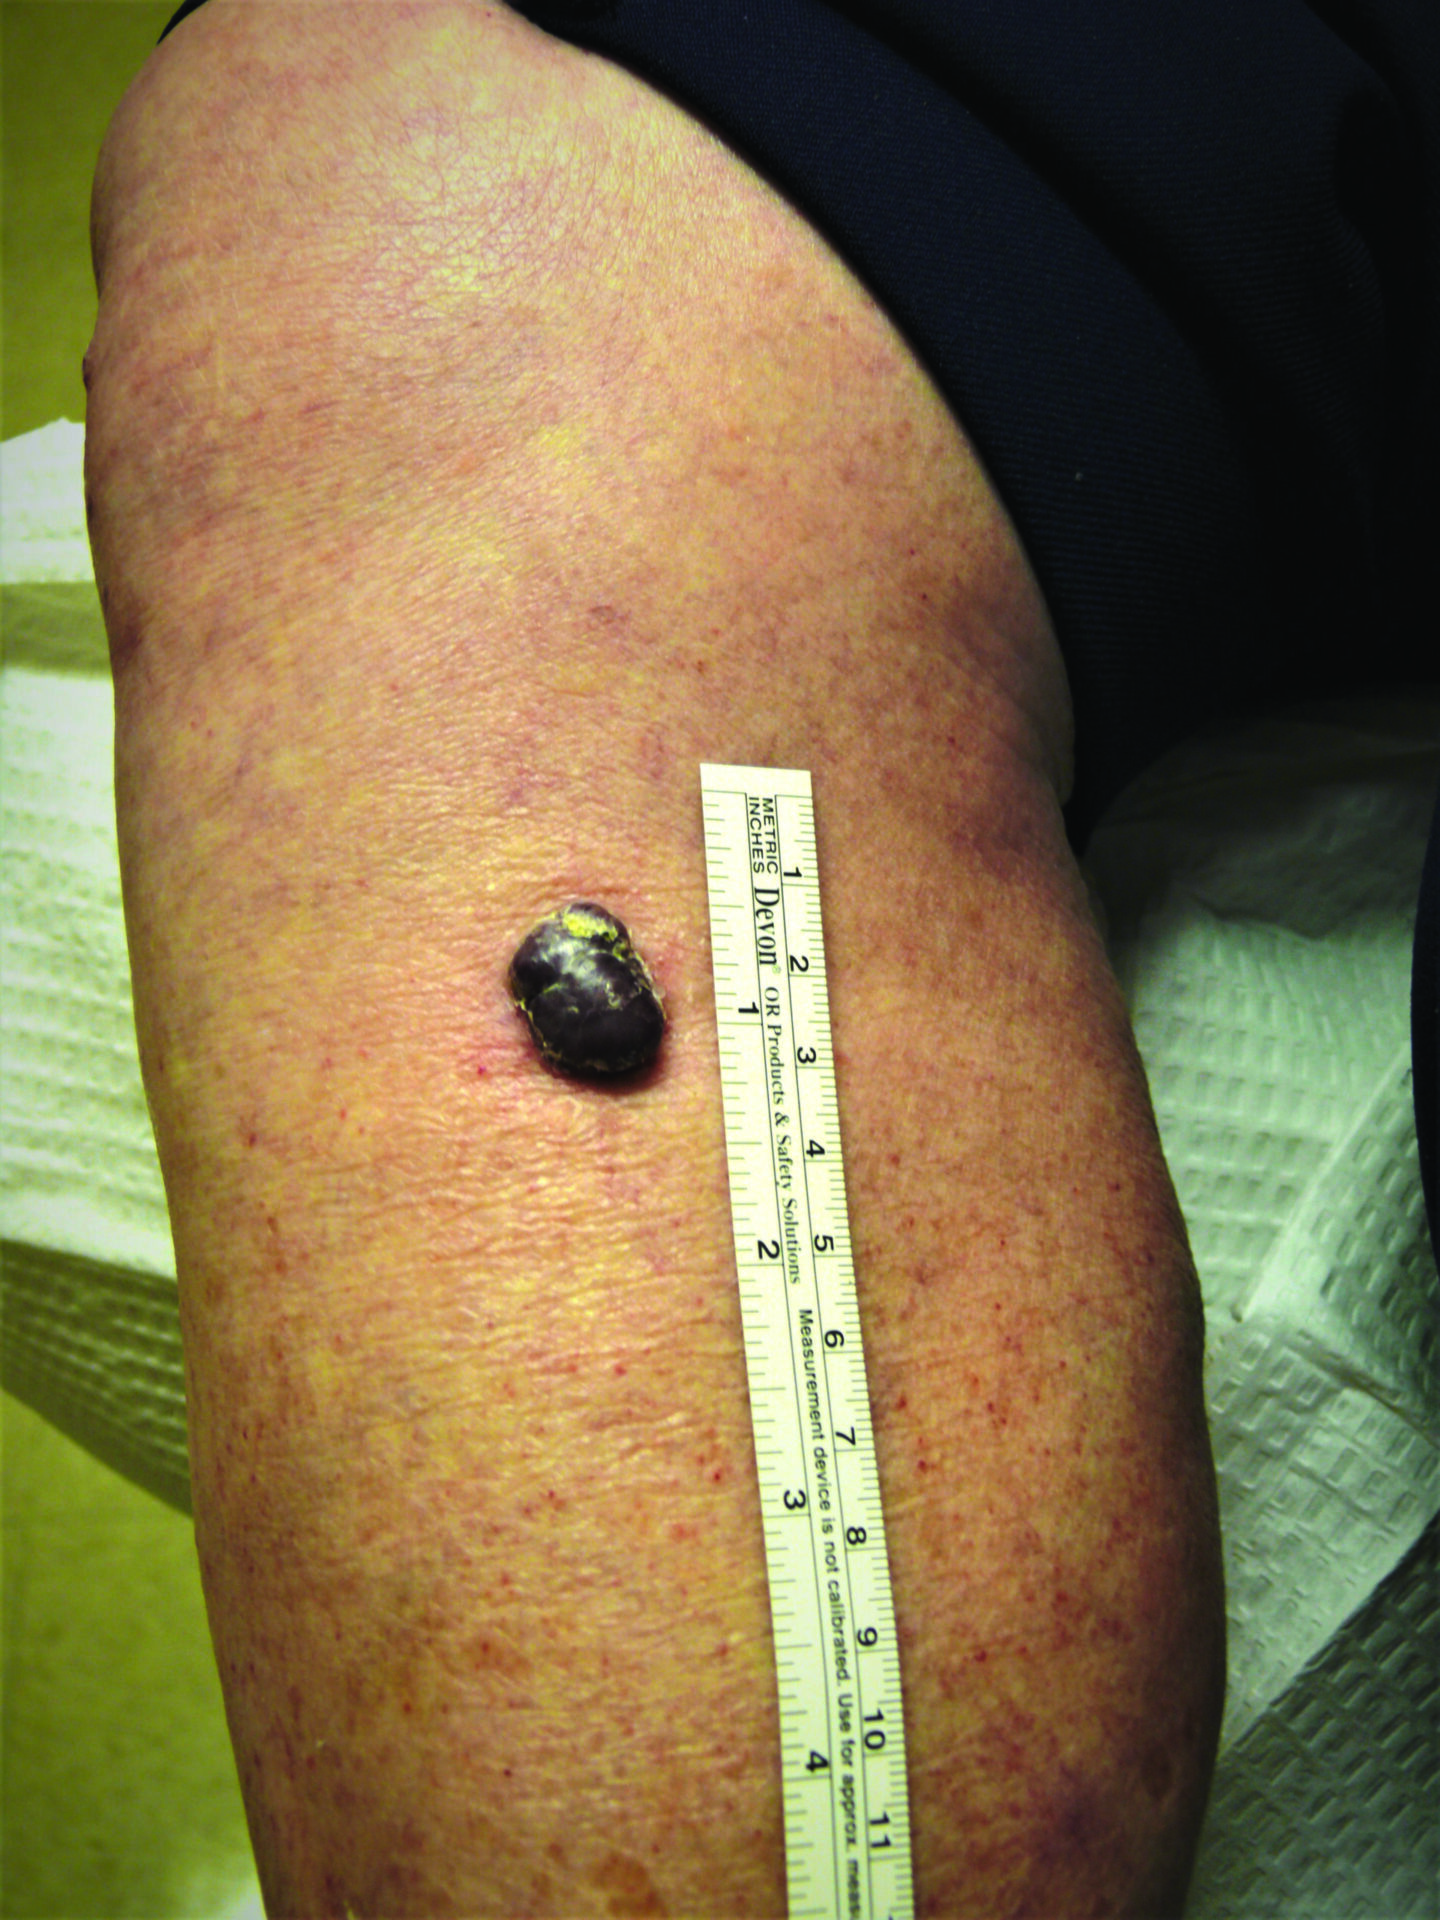

Nodular melanoma on the leg of a Native American woman.

Photo: International Skin Imaging Collaboration

Not a “Boil” but an Advanced Melanoma

Deborah S. Sarnoff, MD

The power of denial can be strong. This man believed the large, dark growth on his back was a boil, despite oozing and bleeding for months. He kept bandaging it and thought it was just slow to heal. When he was finally referred to Dr. Sarnoff, a biopsy and other tests revealed a melanoma so large and deep that it had already spread to the man’s liver and brain. He was referred to an oncologist and began an immunotherapy regimen that did not appear to be working, which happens with some patients. (Thanks to recent innovations, there may be other treatment options, including participation in a clinical trial.) This is a powerful reminder of the importance of early detection.